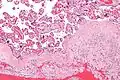

Chronic deciduitis

Chronic deciduitis is a type of long-lasting inflammation that arises in pregnancy and affects the endometrial stromal tissue (decidua).

| Micrograph of a chronic deciduitis, showing the characteristic plasma cells. H&E stain. | |

It is associated with preterm labour.[1] The diagnosis rests primarily on the presence of plasma cells.[2]

High mag.